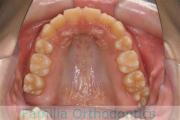

上顎

下顎

前歯の関係など

右側

正面

左側